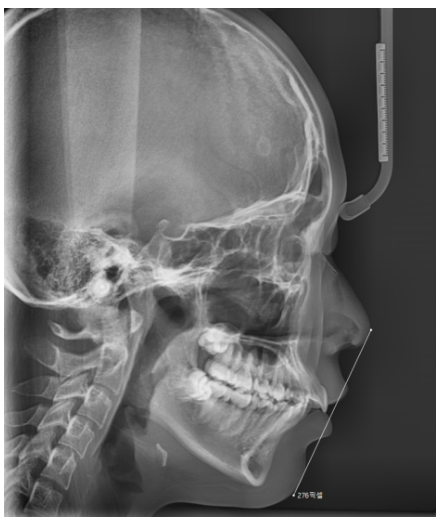

본격적인 교정 시작 전 진단도 해야하고

참고적으로 치아교정은 개인마다 적절한 시작 시기가 다릅니다!!

일반적으로 영구치가 모두 나오는 시기인

초등학교 고학년에서 중학생 시기가 적합합니다.

그렇지만 턱 교정이 필요하냐

치아만 움직이냐

고려해야할 사항들이 있어서

검사를 동반한 상담이 필요하답니다~